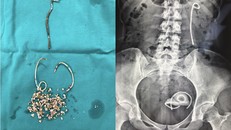

(Ngày Nay) - Ngày 1/3, Bệnh viện Trung ương Quân đội 108 vừa phẫu thuật thành công cho một nữ bệnh nhân bị biến chứng bỏ quên stent niệu quản sau 5 năm.